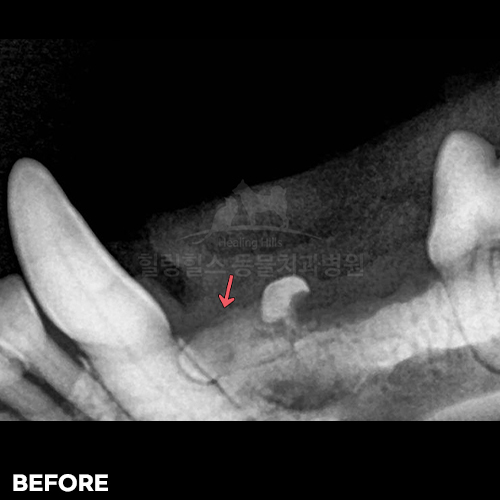

• [강아지 매복치 발치]

샘플